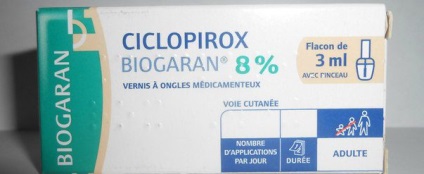

Ótvar emberben együtt pirulák, kenőcsök:

Sömör, amely átment a krónikus formája meglehetősen nehéz kezelni. Ilyen esetekben, megfosztva terápia fokozza az alkalmazás egy speciális összetételű, hogy a fejbőr, amely tartalmazza a szalicilsav. Összetevők kell maradnia a kötést, legalább 48 órán keresztül. Ezután fej jól mossuk, az elváltozások kezelt alkohol-tuning jódot, és miután már alkalmazott gombaellenes kenőcs.